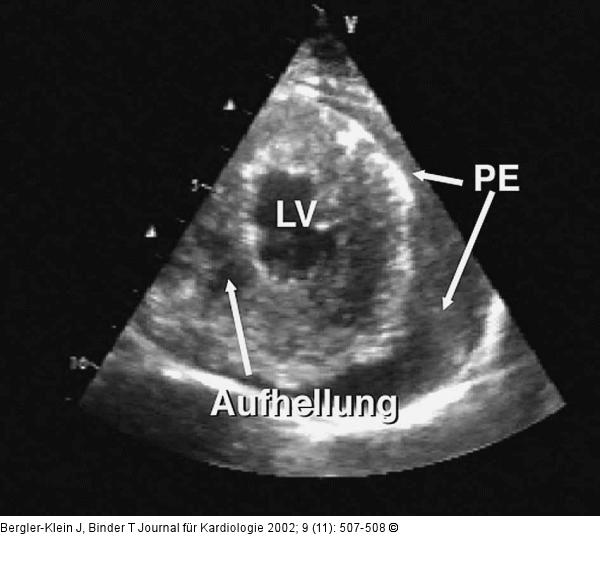

Abbildung 1: Metastasiertes Melanom - Kardiale Manifestation Kurze Achse des linken Ventrikels (LV): Das Myokard ist symmetrisch hypertrophiert und zeigt unregelmäßige Konturierung und noduläre Aufhellungen. Zusätzlich ist ein Perikarderguß (PE) erkennbar. |

Kurze Achse des linken Ventrikels (LV): Das Myokard ist symmetrisch hypertrophiert und zeigt unregelmäßige Konturierung und noduläre Aufhellungen. Zusätzlich ist ein Perikarderguß (PE) erkennbar. |